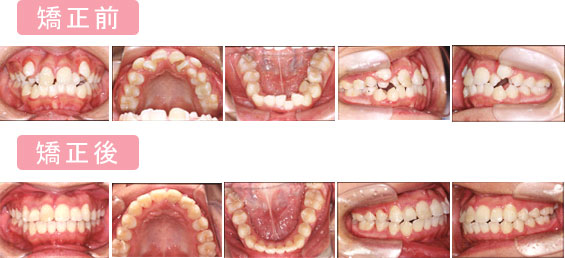

@ガタガタ

歯ならびがガタガタで・・・

口を大きくあけて笑えなくって・・・

<歯を抜かないで治しています>

主訴:ガタガタが気になる

診断名主な症状:Class I crowding

開始年齢:14

装置:R.E.P.+M..B.S.

抜歯部位:非抜歯(0本)

治療期間:22ヵ月

治療費:52万+消費税

リスク(カリエス・歯周病・歯根吸収):矯正治療中・後カリエス等無し